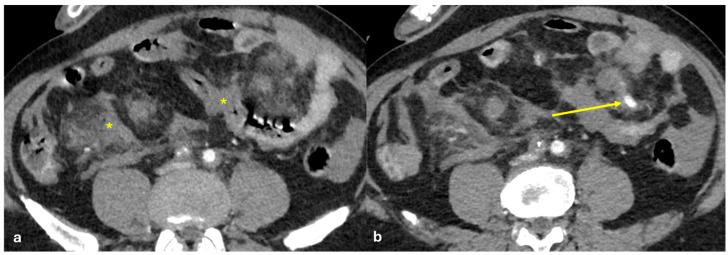

The peritoneum is a thin membrane that lines the abdominal cavity and covers the abdominal organs. It serves as a conduit for the spread of various pathological processes, including gas and fluid collections, inflammation, infections, and neoplastic conditions. Peritoneal carcinomatosis is the most common and well-known pathology involving the peritoneum, typically resulting from the dissemination of gastrointestinal and pelvic malignancies. However, numerous benign and malignant peritoneal diseases can mimic the imaging appearance of peritoneal carcinomatosis. The aim of this review is to revisit the anatomy of peritoneal compartments and elucidate the patterns of peritoneal disease spread. Emphasis is placed on identifying the distinctive imaging features of both neoplastic and non-neoplastic peritoneal diseases that differ from peritoneal carcinomatosis.

腹膜是一层薄的膜,它衬于腹腔内并覆盖腹部器官。它是各种病理过程扩散的通道,包括气体和液体聚集、炎症、感染及肿瘤性疾病。腹膜癌病是涉及腹膜的最常见且广为人知的病理情况,通常由胃肠道和盆腔恶性肿瘤的播散引起。然而,许多良性和恶性腹膜疾病可模仿腹膜癌病的影像学表现。本综述的目的是重新审视腹膜腔室的解剖结构并阐明腹膜疾病的扩散模式。重点在于识别与腹膜癌病不同的肿瘤性和非肿瘤性腹膜疾病的独特影像学特征。